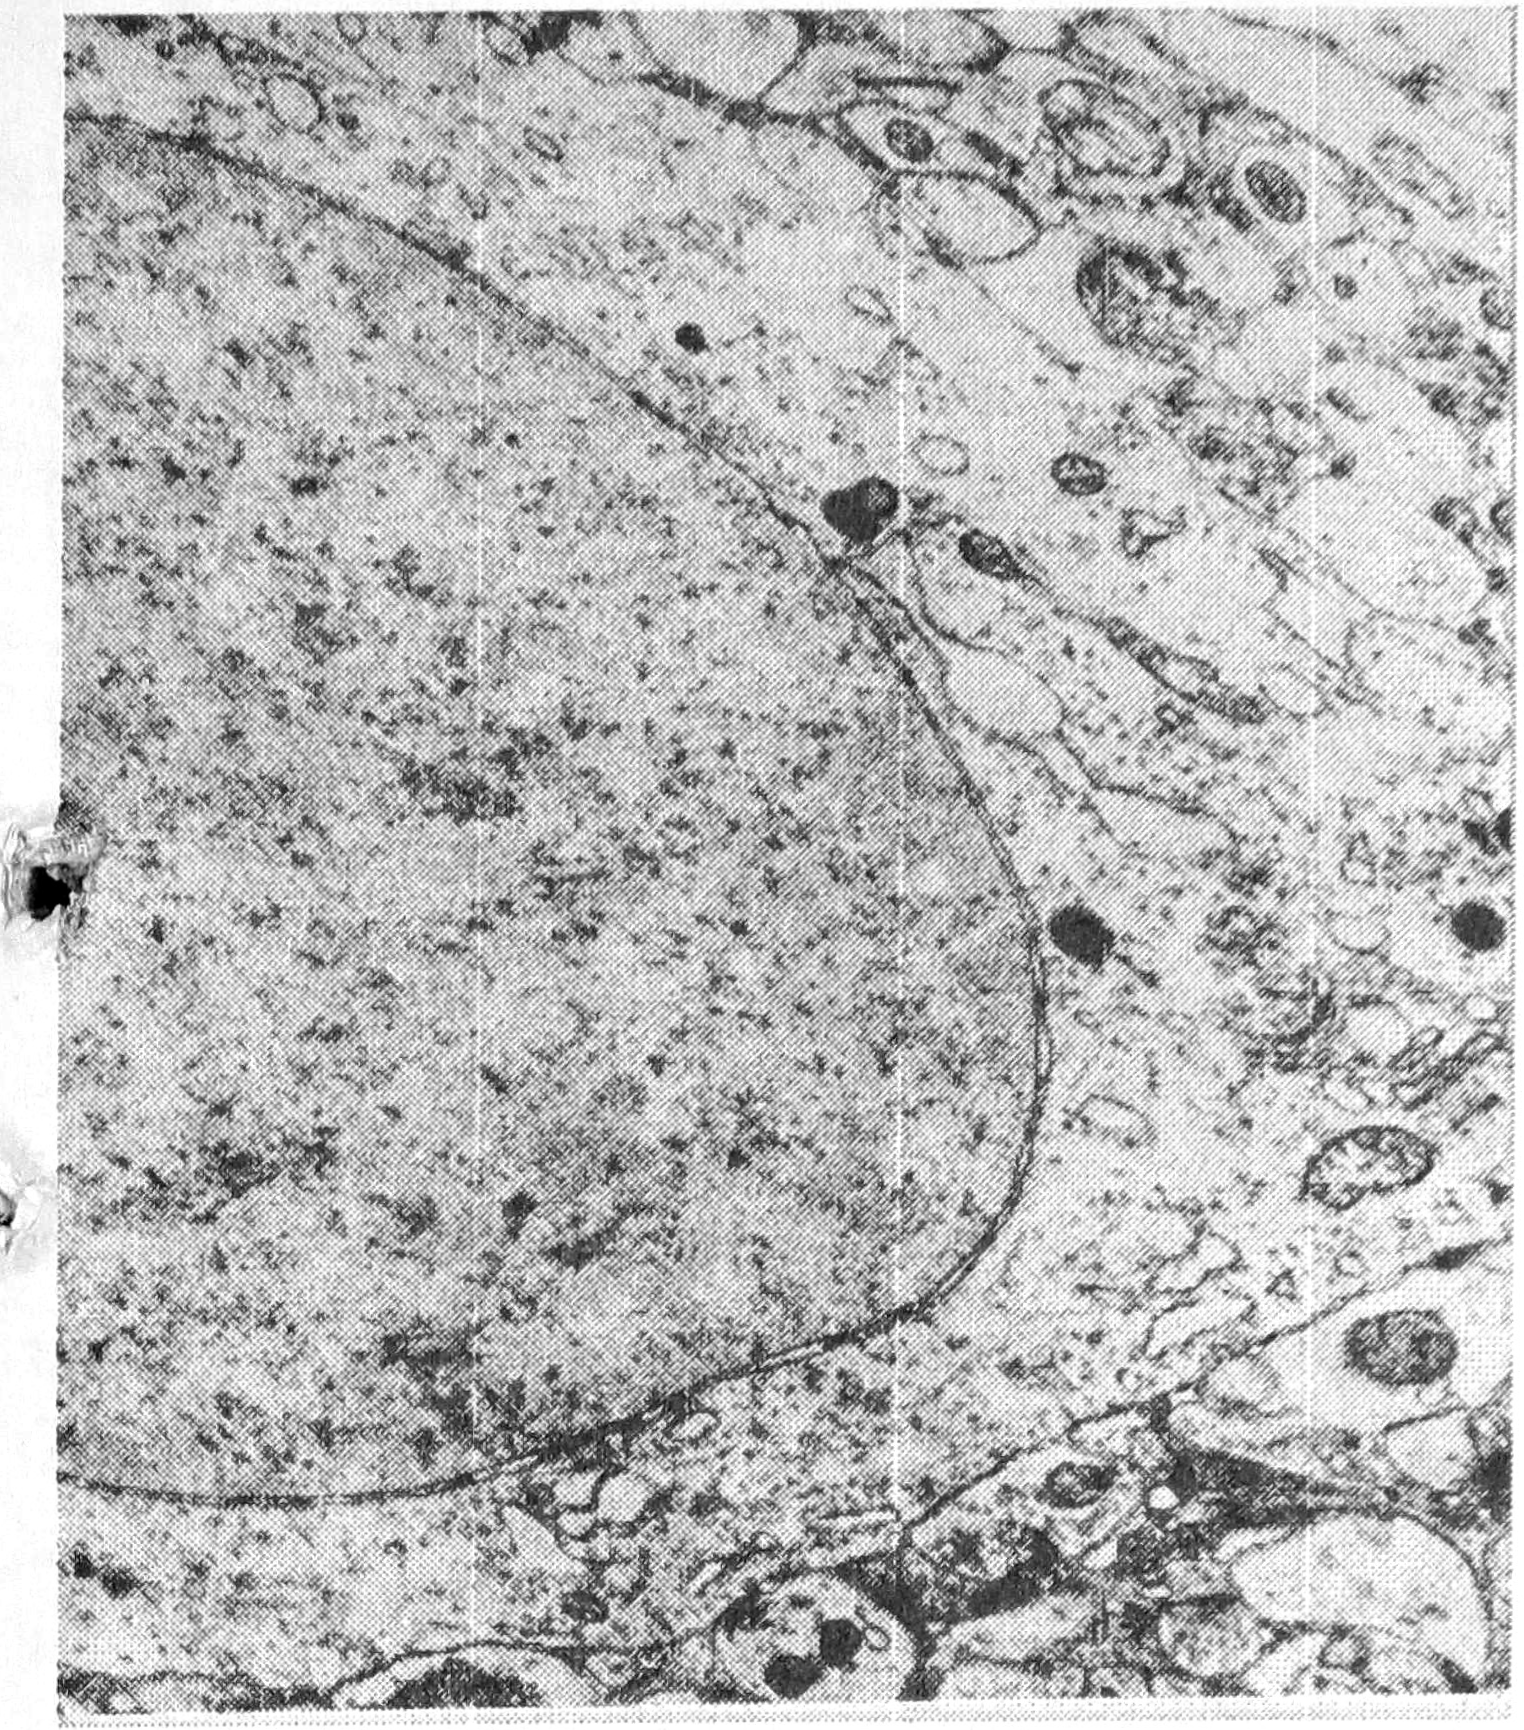

При исследовании коры мозга крыс через час после одного аудиогенного припадка определялось набухание многих корковых нейронов в сочетании с периферическим хроматолизом. Ядра большинства клеток были светлыми, умеренно набухшими, изредка смещенными к периферии клеточного тела. В части гипохромных клеток отмечались признаки репарации в виде смещения ядрышка к периферии ядра, наличия в цитоплазме околоядерного гиперхромного пояса. Встречались отдельные клетки с явлением цитолиза и кариоцитолиза и группы гиперхромных нейронов. На ультраструктурном уровне наблюдались обеднение цитоплазмы органеллами, расширение цистерн эндоплазматической сети, подчас неравномерное, отек отдельных или большинства цистерн аппарата Гольджи, умеренное набухание отдельных митохондрий, увеличение числа лизосом и ядерных пор (рис. 4). Такие изменения популяций нейронов хвостатого ядра обнаруживались при двигательном возбуждении, вызванное фенамином [5]. Дендриты и шипиты корковых нейронов в основном были хорошо импрегнированы, лишь иногда их импрегнация снижалась. В дендритах отмечалось уменьшение числа микротрубочек и нейрофиламентов вплоть до их полного отсутствия и появления вакуолей в дендроплазме. Темные нейроны выявлялись редко, что может указывать на нарушение первичной интеграции приходящих к нейрону импульсов. Имели место умеренное набухание астроцитов с тонкими отростками и явлениями гиперкариохромии. Плотные олигодендроциты не имели видимых отростков. Среди микроглиоцитов встречались формы с фрагментированными отростками. Наблюдалась дистония и расширение просвета части корковых сосудов, набухание сосудистых стенок, периваскулярные отеки, единичные диапедезные кровоизлияния.

Ультраструктура капилляров характеризовалась обеднением органеллами цитоплазмы эндотелиальных клеток, прилежанием к базальной мембране набухших островков периваскулярных астроцитов, содержавших небольшое число митохондрий.

Рис. 1. Ультраструктура нейрона слоя V сенсомоторной коры через один час после одного аудиогенного припадка, х 12000.